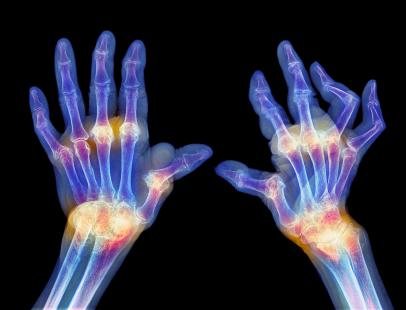

Rinvoq peut être utilisé en monothérapie ou en association avec le méthotrexate (MTX). Son autorisation de mise sur le marché repose sur le programme SELECT composé d’études pivot de phase 3. Ce programme a inclus plus de 4 000 patients souffrant de polyarthrite rhumatoïde active modérée à sévère. Ces études ont évalué l’efficacité et la tolérance chez différents profils de patients, dont les patients en échec ou intolérants aux traitements biologiques ou ayant une réponse inadéquate au MTX.